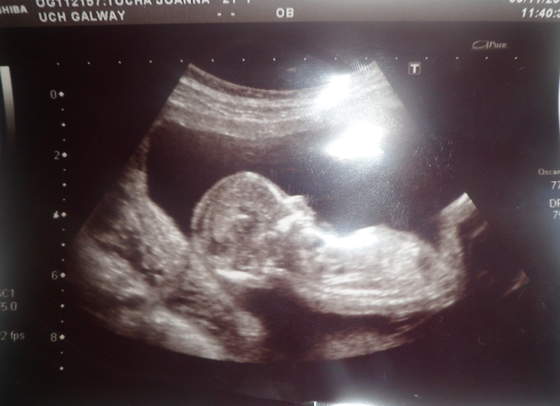

2 bobo

a to jeden na drugim asiia gratulacje, nie wiem co Ci powiedziała Polska gin ale niezależnie czy to bliźniaki jednojajowe, czy dwujajowe mogą być tej samej płci, np. moi chłopcy są dwujajowi, po prostu nie są identyczni.